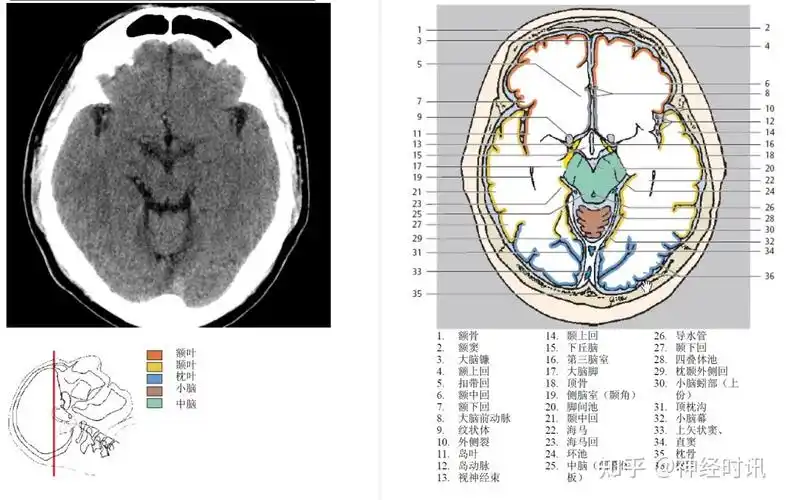

脑池及脑池周围解剖史上最全人手一册